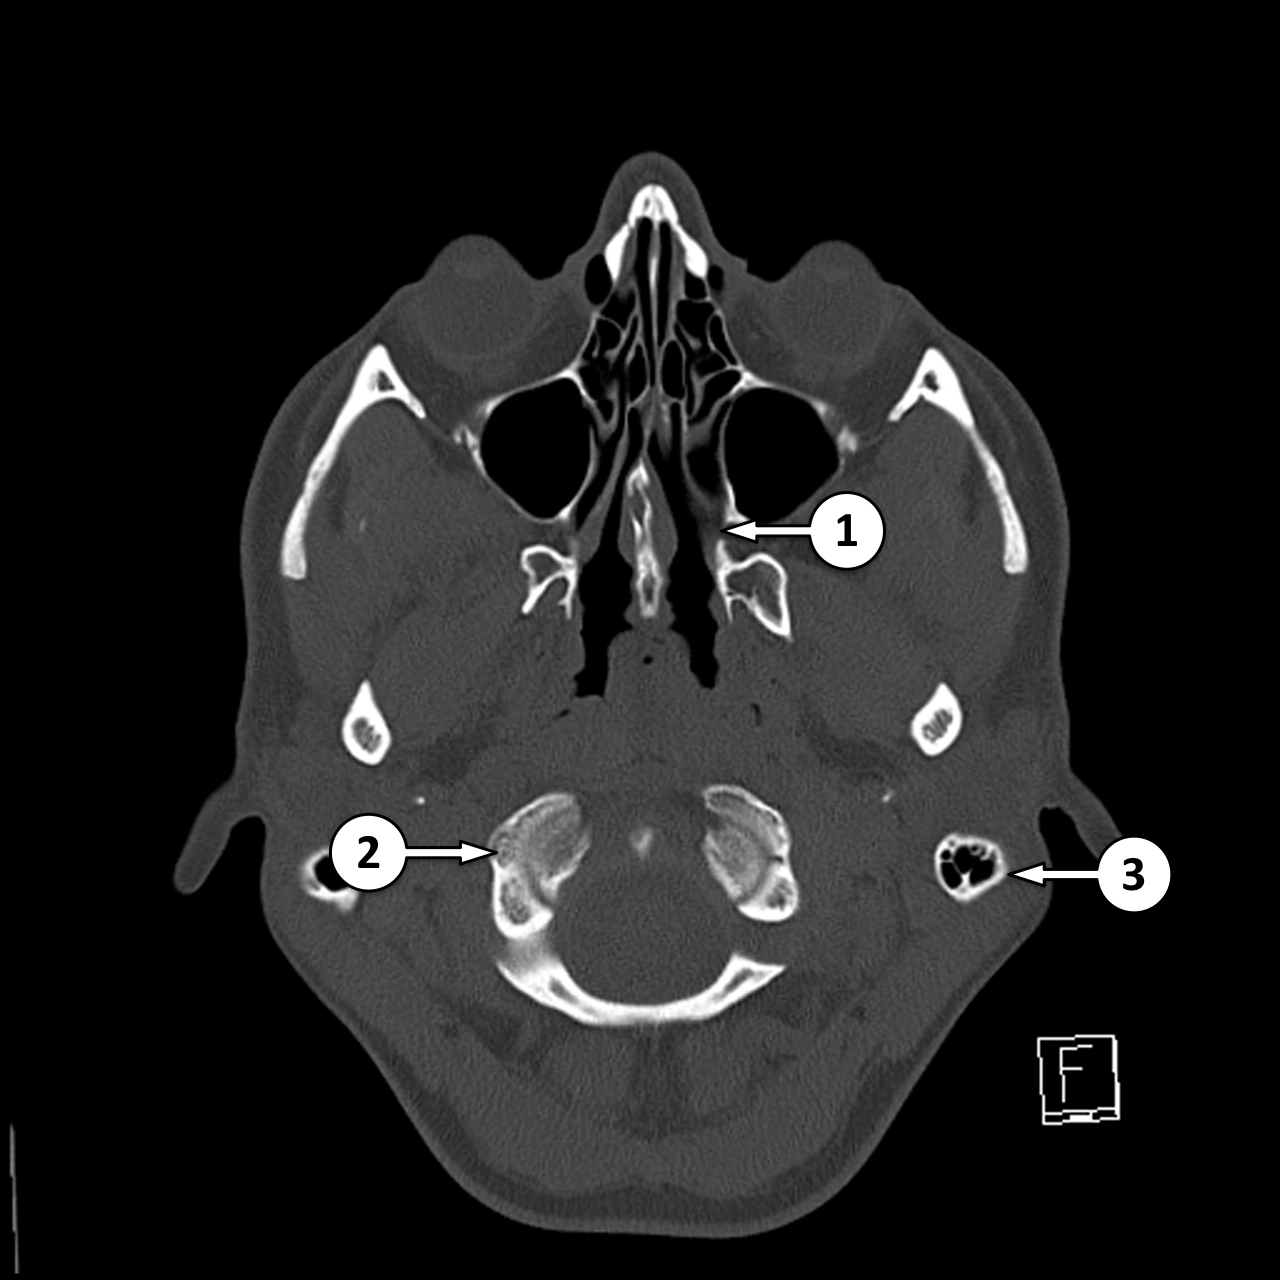

CT Xương thái dương